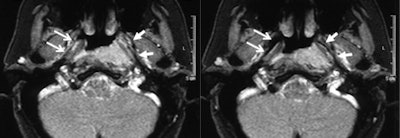

It was possible to evaluate the opening of the eustachian tube during the Valsalva maneuver in all patients. Within the same examination, an underlying problem was identified and its extent delineated in 14 of the 16 patients. In all patients, the anatomical landmarks and structures were clearly depicted and differentiated from pathological abnormalities in the T2-weighted sequence. Involvement of the anatomical structures could be assessed, but the osseous part of auditory tube was depicted with less good image quality than the other parts. In this region, the amount of soft tissue is small and consists only of the mucous membrane, connective tissue, and the periosteum.

Using a 1.5-tesla ACS-NT system from Philips Healthcare, the researchers performed MRI exams on16 patients (seven female, nine male) in the supine position using a standard head coil that was 30 cm in diameter. The age of the patients ranged from 26 to 82 years (mean 55.6 ± 13.1 years standard deviation). Five patients had carcinoma of the neck region, and the remaining 11 patients had clinical signs of sinusitis.

"Owing to its high soft-tissue contrast resolution, MRI represents an excellent method to assess anatomical landmarks and abnormalities in and around the auditory tube. Also, information of eustachian tubes opening and closing, its functional state, is clearly visible with the aid of appropriate protocols while the patients perform a Valsalva maneuver," they stated. "To date, functional studies of the eustachian tube have only been performed in normal subjects, but not in patients with clinical symptoms of nonopening of the eustachian tube and abnormal tympanometry."